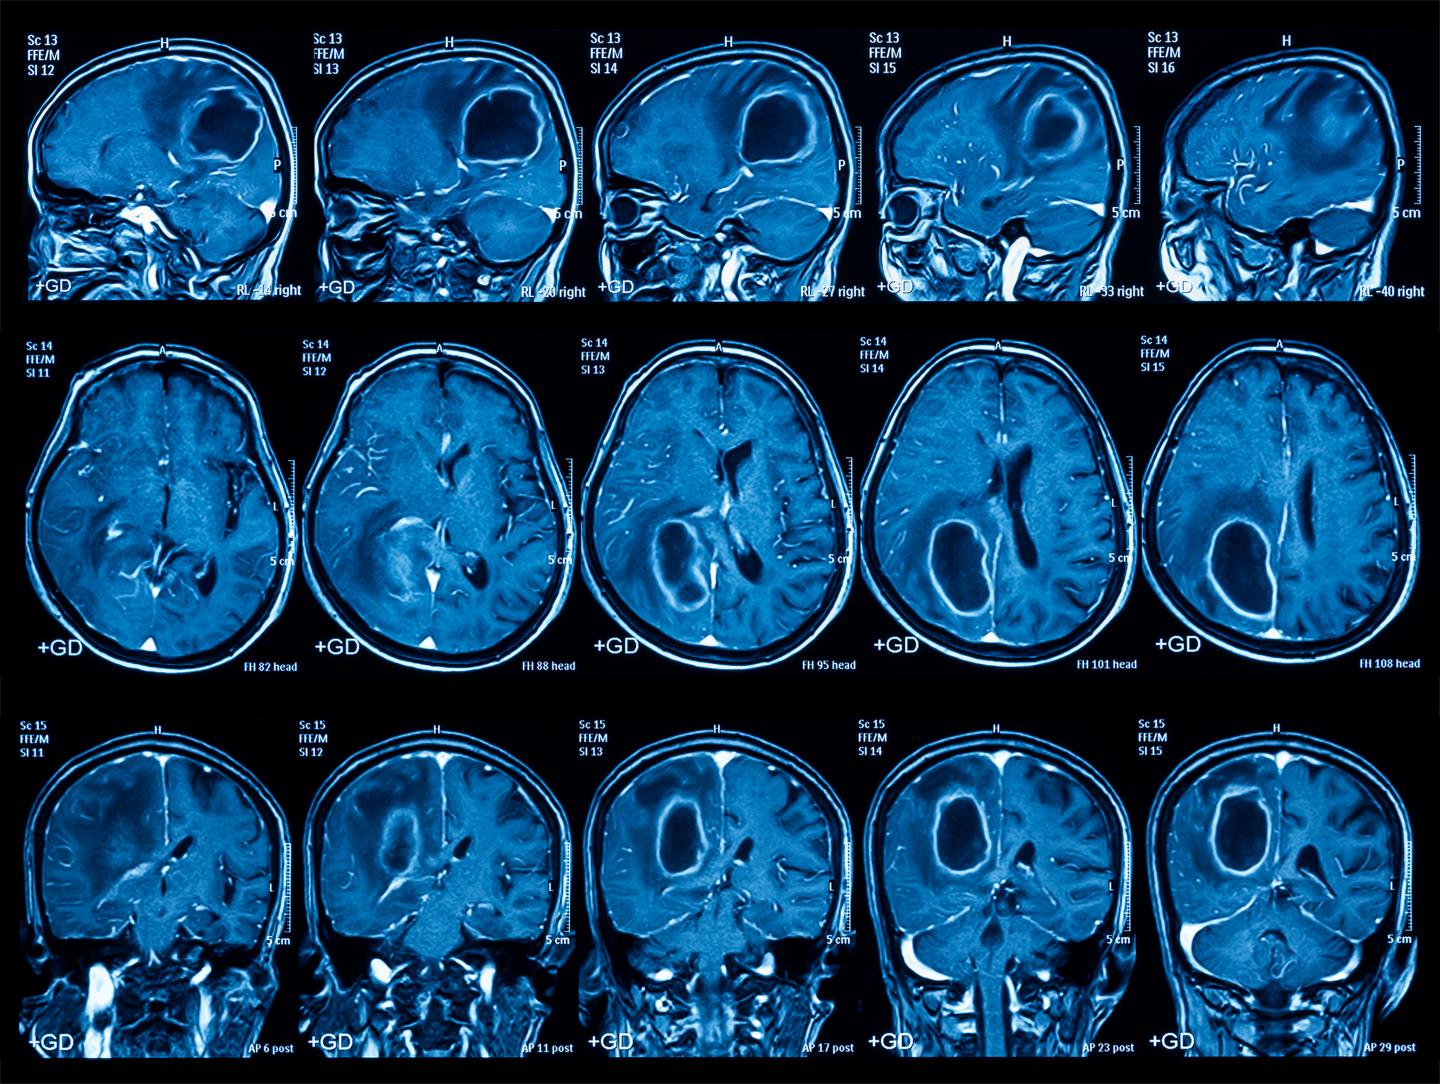

Imaging is often the first step to diagnosis, so it must be accurate and quick. KMC’s Medical Imaging Department is equipped with cutting-edge technology to visualize what is happening inside your body. “Our motto is ‘see clearly, treat precisely,’” says our Radiology Director who leads an excellent team of radiologists and technicians, many of whom trained abroad.

Our high-powered machines take crystal-clear images, from head to toe. Our suite includes a 3T MRI (for detailed brain, spine, and soft tissue scans), a 128-slice CT scanner (ideal for bones, chest, and vascular imaging), and an advanced digital X-ray and mammography system high- resolution ultrasound technology ( perfect for abdominal, pelvic, vascular, and obstetric imaging, fluoroscopy for dynamic real – time imaging , and hysterosalpingography for evaluating fertility - related conditions. Every image is reviewed by board-certified radiologists who immediately communicate results to your doctor.